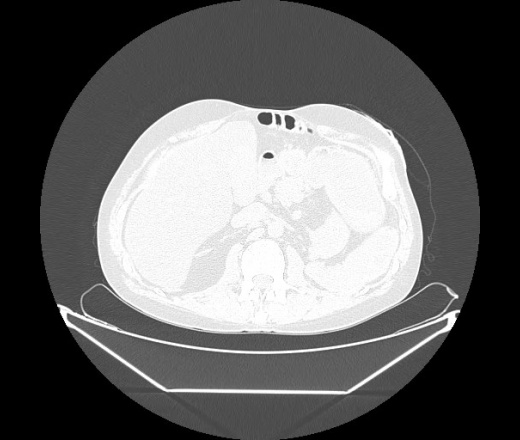

М. 1984 г.р.  Лихорадка 39, кашель , одышка.. и надоевший всем вопрос- "типично ли для ковид?" ( в настоящее время на него обязательно нужно дать ответ в своем протоколе)

На мой взгляд нетипично для ковид: много центрально-расположенных поражений, лобарное поражение нижней доли слева. 50/50

Не типичая картина для ковид.

КТ-признаки двусторонней бактериальной пневмонии.

Все верно, здесь абсолютно нетипичная картина, несмотря на матовое стекло с ретикулярными изменениями, но почему-то  посчитали иначе. Кстати,  "малыша" не заметили)?